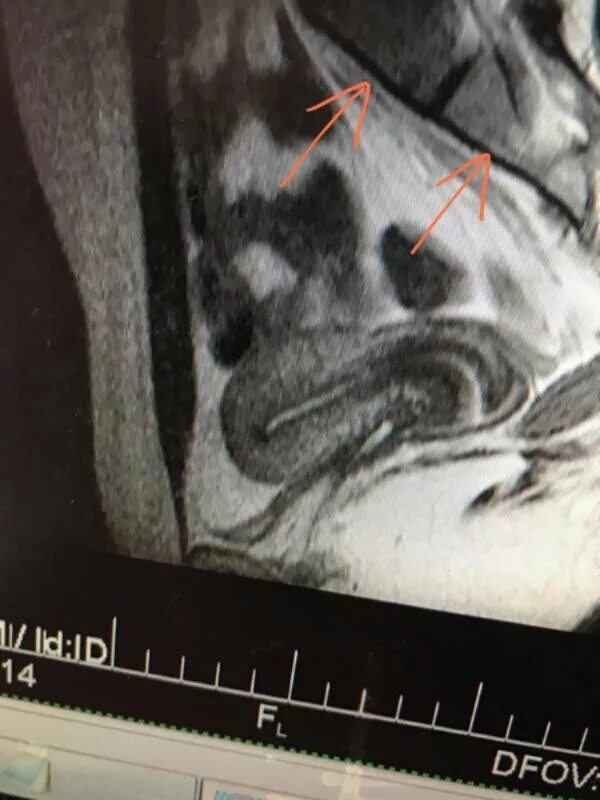

Матка расположена в anteflexio что это